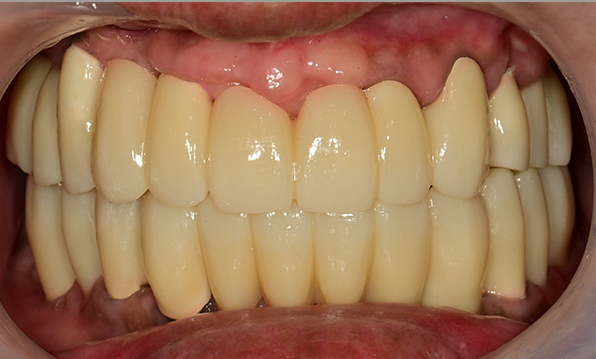

치료기간 : 2021.04.12~2021.09.15